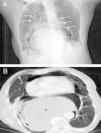

We report the case of a 96-year-old woman with a history of high blood pressure and hiatal hernia who presented with severe epigastric pain and coffee ground vomiting of 6h duration. On physical examination, abdominal distention and epigastric tenderness were observed. Chest radiography revealed a gastric chamber distended into the chest cavity and pneumomediastinum. Thoracoabdominal CT (Fig. 1) showed gastric chamber distention at a thoracic level with gastroesophageal and gastroduodenal junction above the esophageal hiatus, accompanied by air and fluid collections in the mediastinum, along with subcutaneous emphysema. These findings were consistent with gastric perforation secondary to volvulus in a patient with giant hiatal hernia. Due to the advanced age of the patient, surgery was ruled out, and she died a few hours after admission.